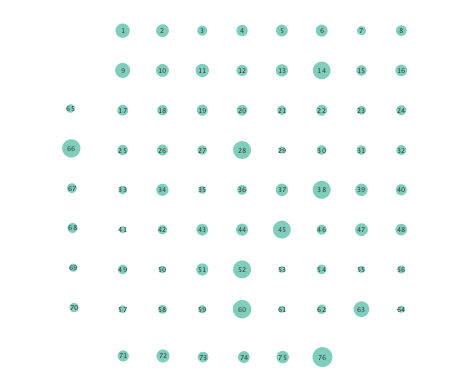

In order to assess the information-routing abilities of brain regions before and after seizure onset, comparisons of the so-termed betweenness centrality were done. Betweenness centrality of a node computes the fraction of shortest paths between all node pairs that traverse the given node, and it is useful to identify the key information transmitting hubs in a network; see e.g., [24] for more details. The per-node betweenness centrality for each inferred network are depicted in Figure 4, with node radii similarly encoding the computed values. Little variation between preictal and ictal betweenness centralities is seen for the linear model (Figures 4 (a) and (b)), while variations are slightly more marked for the K-SVARM, see Figures 4 (c) and (d). It can be seen that modeling nonlinearities reveals subtle changes in information-routing capabilities of nodes between preictal and ictal phases.

Clustering coefficients are generally used to quantify network cohesion, the tendency for nodes to form groups or communities. Comparison of such coefficients between the preictal and ictal phases may reveal differences in cohesive behavior after onset of a seizure. In the present paper, a per-node clustering coefficient is adopted, and it computes the fraction of triangles in which a node participates out of all possible triangles to which it could possibly belong [24]. Note that a triangle is defined as a fully connected three-node subgraph. Figure 5 depicts clustering coefficients per electrode obtained during the ictal and preictal phases of the ECoG time series. While both the linear and nonlinear models yield changes in the computed coefficients, most nodes have lower clustering coefficients upon seizure onset in the networks inferred via the K-SVARM.

Finally, Figure 6 depicts the closeness centrality computed per node in the inferred networks. Closeness centrality measures how reachable a node is from all other nodes, and is generally defined as the reciprocal of the sum of geodesic distances of the node from all other nodes in the network; see also [24]. Once again, Figure 6 depicts a more general decrease in closeness centralities after seizure onset in networks inferred by the nonlinear SVARM, as compared to the linear variant. This empirical result indicates a change in reachability between regions of the brain during an epileptic seizure.

Moreover, the performance of K-SVARM with data-driven kernel selection was also tested. Figure 7 illustrates the per node degree as well as the closeness centrality of networks inferred from preictal and ictal phases. Consistent with Figures 3 and 6, Figure 7 again reveals universal decrease in node degrees as well as closeness centrality at seizure onset.